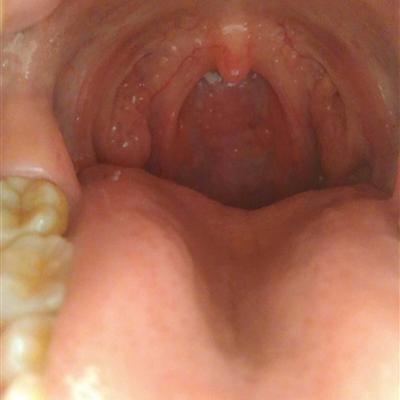

Second: there are many patients with bad breath. Generally, if they have dental problems, such as gingivitis, periodontitis, oral mucositis, and bad breath caused by tooth decay, periodontal disease, caries and other factors, the problem is quite serious. Timely treatment is the key to the problem.

Third: halitosis is generally caused by not paying attention to oral hygiene, which is an important oral problem. Many people will also have halitosis if they have stomach heat.